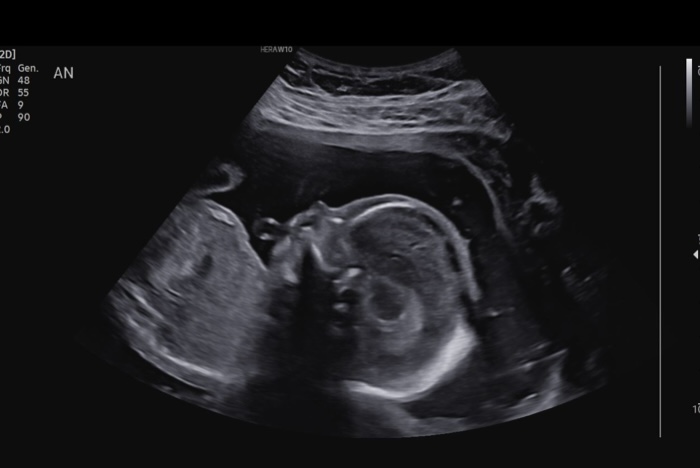

We had our halfway ultrasound and got to see our wiggly little guy! He was moving all over, but then refused to move when the tech needed him to so she could get a better angle. Such a stubborn little boy! Everything is measuring perfectly and all looks great, which is such a relief and we are so grateful! Little guy is moving a LOT now and I can feel him all the time, which makes it much more real that we’re actually having a baby!